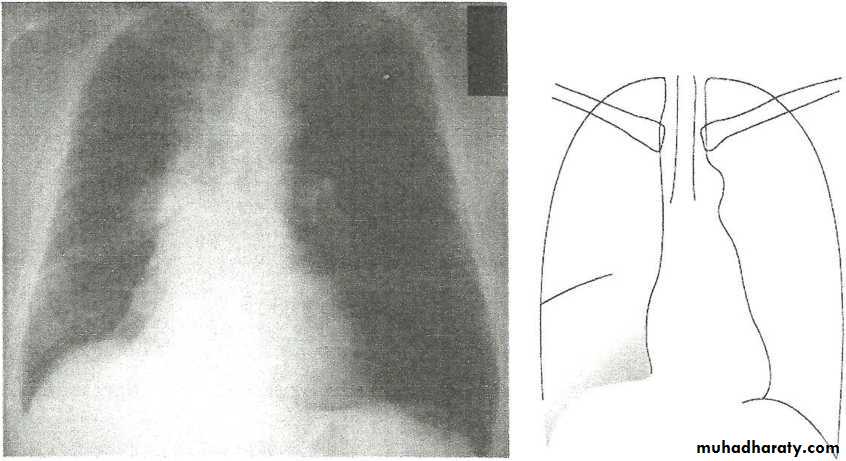

Tension pneumothorax.

On a posteroanterior chest x-ray (A), the left hemithorax is very dark or lucent because the left lung has collapsed completely (white arrows).

The tension pneumothorax can be identified because the mediastinal contents, including the heart, are shifted toward the right, and the left hemidiaphragm is flattened and depressed. A computed tomography scan done on a different patient with a tension pneumothorax (B) shows a completely collapsed right lung (arrows) and shift of the mediastinal contents to the left.